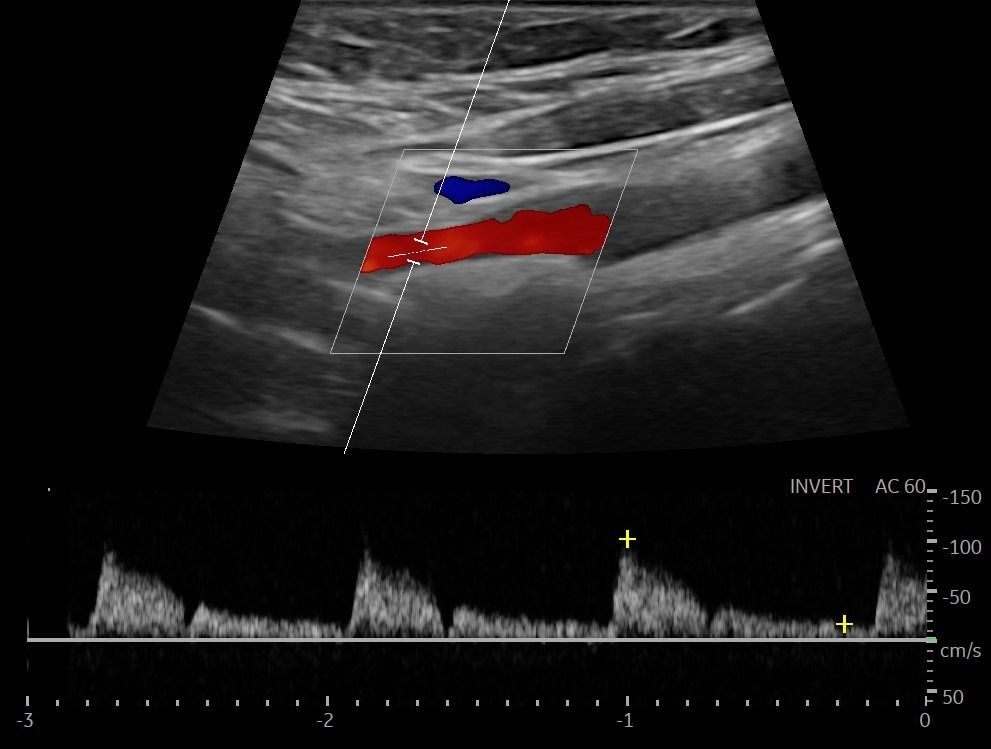

- Έγχρωμο Doppler: Αξιολογεί την ταχύτητα και την κατεύθυνση της ροής του αίματος, προσδιορίζοντας την ύπαρξη και το ποσοστό στένωσης των αρτηριών.

- Παλμικό Doppler: Παρέχει πληροφορίες για τις διακυμάνσεις της ροής του αίματος, βοηθώντας στην αναγνώριση πιθανών αιμοδυναμικών διαταραχών.